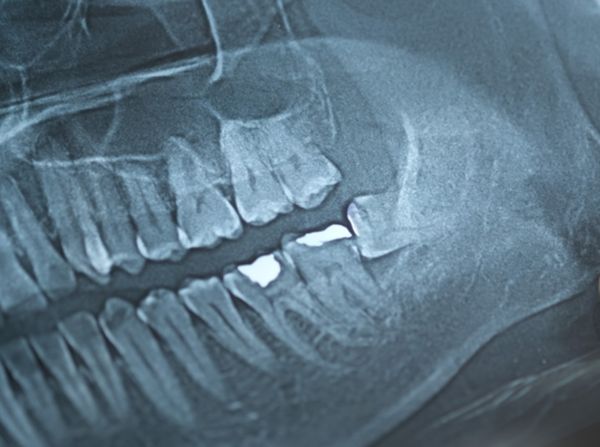

I had my first tooth cavity in my late teens. The dentist used a silver-mercury amalgam as the filling material. Amalgams contain silver and approximately 50% elemental mercury along with small amounts of tin and copper, all mixed before filling a tooth. Amalgam has been a dental standard for almost 150 years. It forms a barrier to further tooth decay with the mix keeping the mercury bound so that it never becomes a health risk. Or so we thought.

When a press release I received on November 4, 2025, talked about dental amalgams and elemental mercury as a threat, I decided it was worth investigating. The release came from the International Academy of Oral Medicine and Toxicology (IAOMT). It was entitled “Dental Amalgams and Blood Mercury Concentrations in American Adults” and presented data from a CDC study stating that approximately 104 million Americans with mercury amalgam dental fillings were at risk of elevated blood mercury levels to dangerous thresholds. The study revealed that adults between the ages of 18 and 70 with amalgam fillings had significantly higher blood inorganic mercury levels than those without. The number of filled cavities where amalgam was used strongly correlated with increased mercury levels in blood. The CDC study estimated that 16 million adults were being exposed to mercury vapour doses exceeding U.S. EPA safety limits. Mercury in the blood was the key to delivering the toxin in tissues and cells throughout the body, leading to increased risk of asthma, arthritis, hearing loss, neurological disorders, and perinatal death.

Interestingly, these conclusions had been stated before. A 2020 research report commissioned by the U.S. Food and Drug Administration (FDA) led to a recommendation back then that silver-mercury amalgams were a risk to pregnant women and their fetuses, nursing mothers, children under six, individuals with mercury allergies, and those with neurological or kidney impairments.

For patients, the IAOMT is recommending that they talk to their dentists and doctors about the option to safely remove amalgam fillings where old fillings are breaking down and in need of replacement. The IAOMT offers a training program called the Safe Mercury Amalgam Removal Technique (SMART) that can protect both patients and dental staff from exposure to mercury vapour.